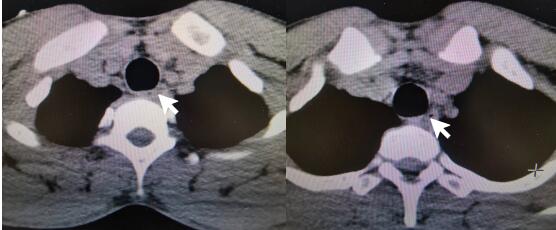

患者接触史明确,诊断为“磷酸铵盐干粉灭火剂中毒”。入院后禁食,胃肠减压,给与保护胃黏膜、抑制胃酸分泌、保护肝功能、导泻、水化碱化以及营养支持对症治疗。根据每日血清电解质结果调整补充量。约1 d后,血磷、血钾、碱剩余恢复正常范围,腹部CT:结肠内高密度影(见图 2)。心脏、双下肢静脉、腹部及泌尿系B超未见明显异常。2 d后外周血白细胞数恢复正常范围。肺部CT示右肺下叶少许炎性灶。3~4 d后血钙、肌酸激酶同工酶、超敏C反应蛋白恢复正常范围。头颅CT及MRI未见明显异常。脑电图示轻中度异常,右侧额颞部中央部略偏胜,脑地形图示右侧额颞部中央部δ频段功率相对偏高。考虑患者口咽部疼痛较前缓解,粪便隐血转阴,改为半流质饮食。5 d后,肌酸激酶恢复正常范围。食管CT:食管局部管壁稍水肿增厚,管腔狭小(见图 3)。患者住院期间未使用抗生素,转氨酶、肌酐均在正常范围,予第6天出院。本病例报道经浙江大学医学院附属第一医院伦理委员会批准,且所有临床资料均获得患者本人授权(伦理审批号:2022380)。

| 图 2 患者入院1 d后腹部CT平扫示结肠内高密度影 |